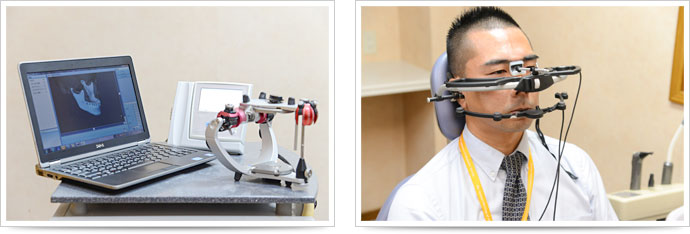

当院では、従来のような「人の感覚」に頼っていた咬み合わせの診査診断ではなく、咬み合わせ機能分析装置による診査診断システムを導入しております。このシステムの導入により、従来は困難とされていた「顎の動き」や「咬み合わせ位置・力」を測定することが可能となりました。

顎の動きを分析 -「アルクスディグマ2」

当院では、世界的メーカーであるドイツKaVo社が開発した「アルクスディグマ2」を導入しております。アルクスディグマ2は超音波測定によるデジタル式顎運動計測装置です。

この機器の特徴として、患者様にヘッドフレームを装着することで、人の感覚では分からない顎の細かい動きを分析することができます。さらに、モニタ上で顎の動きをリアルタイムで見ることが出来ますので、患者様にも分かりやすく説明することができます。

立体的に記録された顎の運動記録を右のような咬合器に落とし込み、反映させることができます。

立体的に記録された顎の運動記録を右のような咬合器に落とし込み、反映させることができます。

患者さんの顎の動きと全く同じ動きをする咬合器(作業台)を活用することで、より精密な咬み合わせの調整が可能になります。